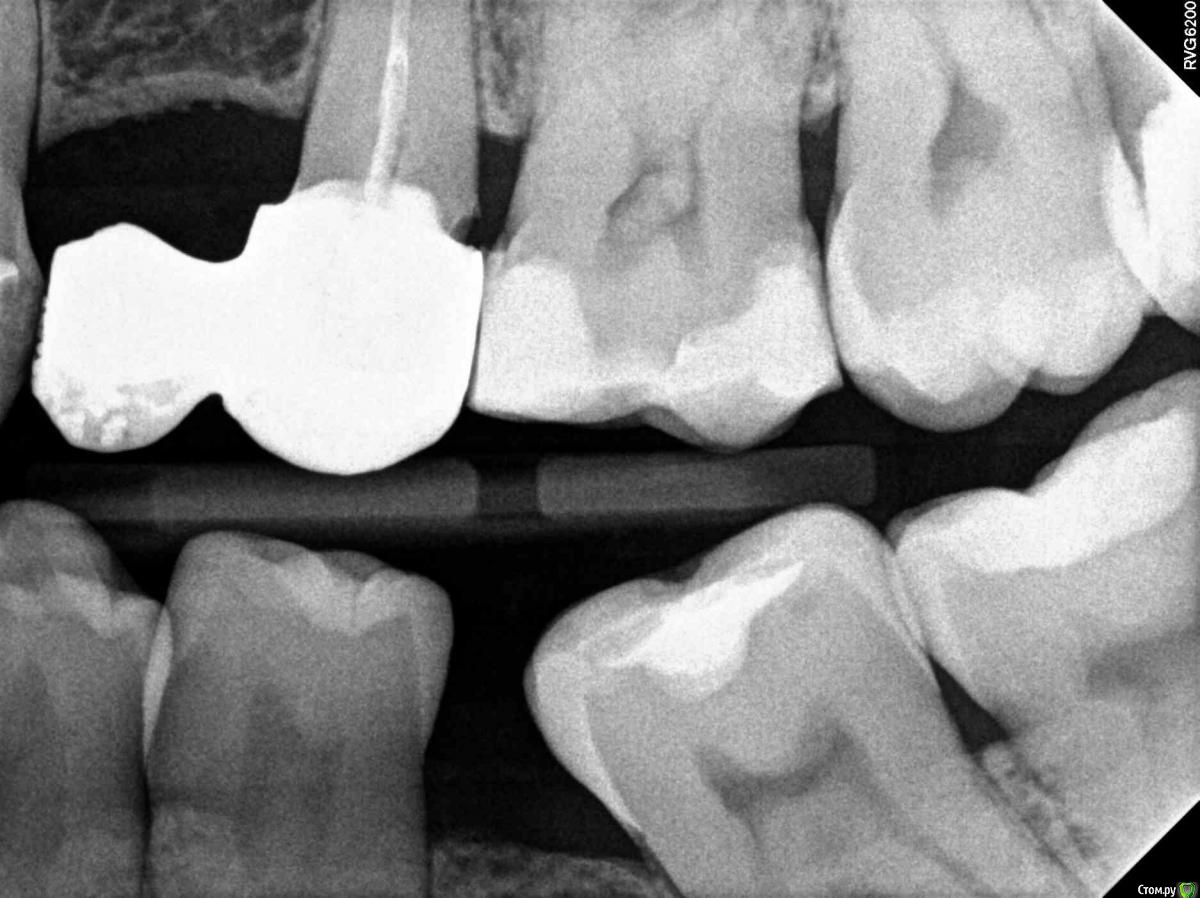

rex11 Опубликовано 11 января, 2017 Поделиться Опубликовано 11 января, 2017 Здравствуйте, уважаемые врачи.Скажите, пожалуйста, что вы видите на этом срезе КТ?На мой взгляд, здесь в зубе 2\7 средний кариес, а в зубе 3\7 маленький кариес под пломбой. Права ли я и насколько срочное лечение требуется в этих случаях? Заранее больое спасибо! Ссылка на комментарий

anvladd Опубликовано 11 января, 2017 Поделиться Опубликовано 11 января, 2017 2.5,2.6 кариес. 2.7 ?медиально. 3.7 возможно под пломбой Ссылка на комментарий

anvladd Опубликовано 12 января, 2017 Поделиться Опубликовано 12 января, 2017 25 под коронкой на задней поверхности26 на передней поверхности под пломбой рядом с 2527 медиально тоесть передн п-овть,средн кариес,но по снимку не всегда понятно нужно зондировать 1 Ссылка на комментарий